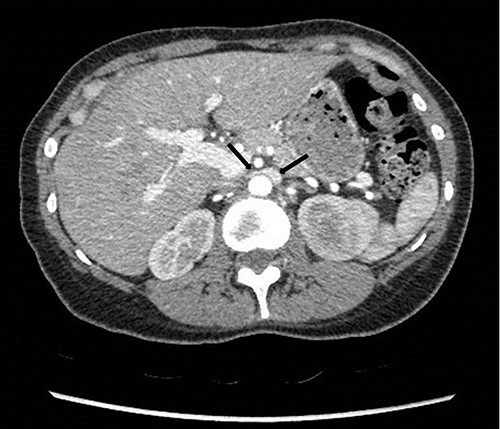

To investigate the bleeding source, she subsequently had a CT renal angiogram 3 days later that showed a narrow angle between origin of SMA and the aorta (Fig. 3) with multifocal areas of hypoattenuation throughout the left renal cortex (Fig. 4). It showed a compression ratio of 3.25 (diameter of pre-compressed vein =6.5 mm; diameter of compressed vein =2 mm) (Fig. 5).

Computed tomography angiogram on presentation, sagittal view showing origin of SMA (left arrow) and the aorta (right arrow) with the compressed LRV in the narrow angle (middle arrow).